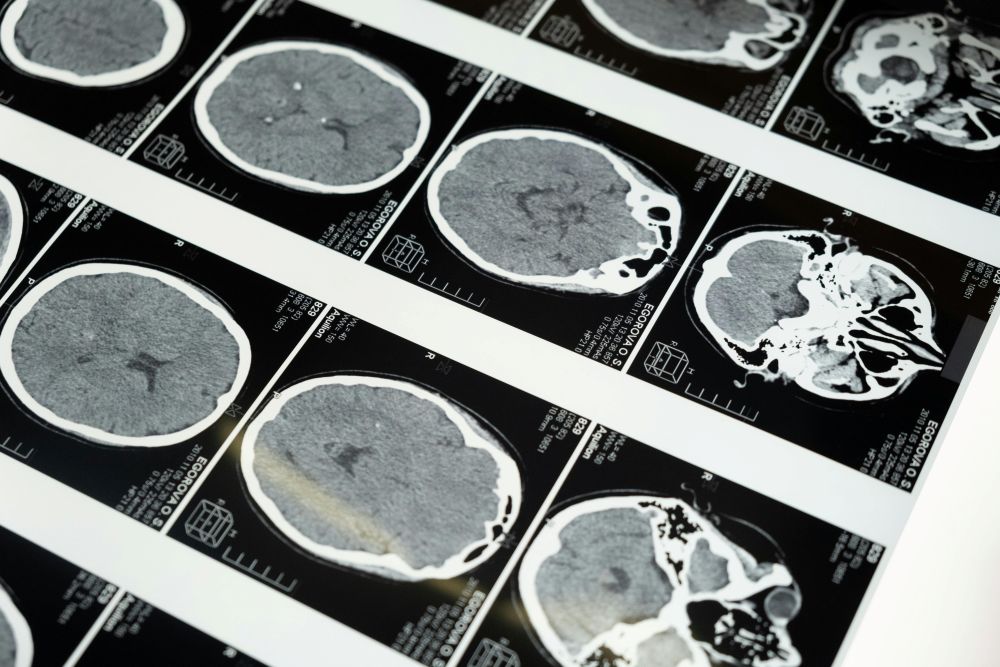

A research team from Georgia State University has taken an important step toward showing how brain biology, even its smallest parts, build larger systems that guide thought, emotion, and everyday behavior. The work draws from several areas of science and brings together brain scans, genetic brain biology records, and molecular maps to form a picture of how tiny structures help shape broader patterns seen during mental activity. The findings come from a project involving the TReNDS Center, a joint effort linking Georgia State, Georgia Tech, and Emory University. The center focuses on tools that connect imaging data with biological features that may influence thinking, mental health, and age-related changes.

Guided by senior author Vince Calhoun, the team studied how cells, chemical messengers, and energy-producing structures relate to brain networks often seen in fMRI scans. Calhoun explained that large networks do not form at random. Instead, they grow from a kind of hidden blueprint based on chemical and cellular gradients. These gradients help set up the pathways through which different areas of the brain share information. Each type of data gives a partial view, but when combined, they form a picture showing how the brain organizes itself from the ground up. The study suggests that network activity does not stand apart from biology. Instead, it may serve as the link between molecular details and behavior.

The project made use of dynamic connectivity, which tracks shifting activity patterns in real time. These patterns were studied along with maps showing where certain cell types cluster, where chemical messengers such as serotonin and dopamine are most active, and where mitochondria are working hardest. The combination offered insight into how different levels of the brain support each other. A statistical method known as mediation analysis helped show that networks may act as bridges between biology and behavior rather than simply moving in parallel. This may help explain how small cellular shifts can guide larger changes in thinking.